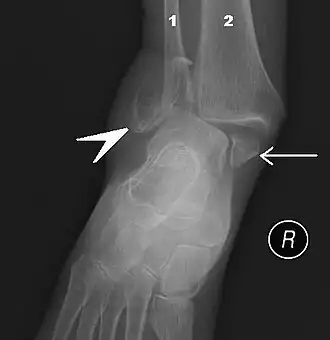

Fracture bimalléolaire de la cheville.